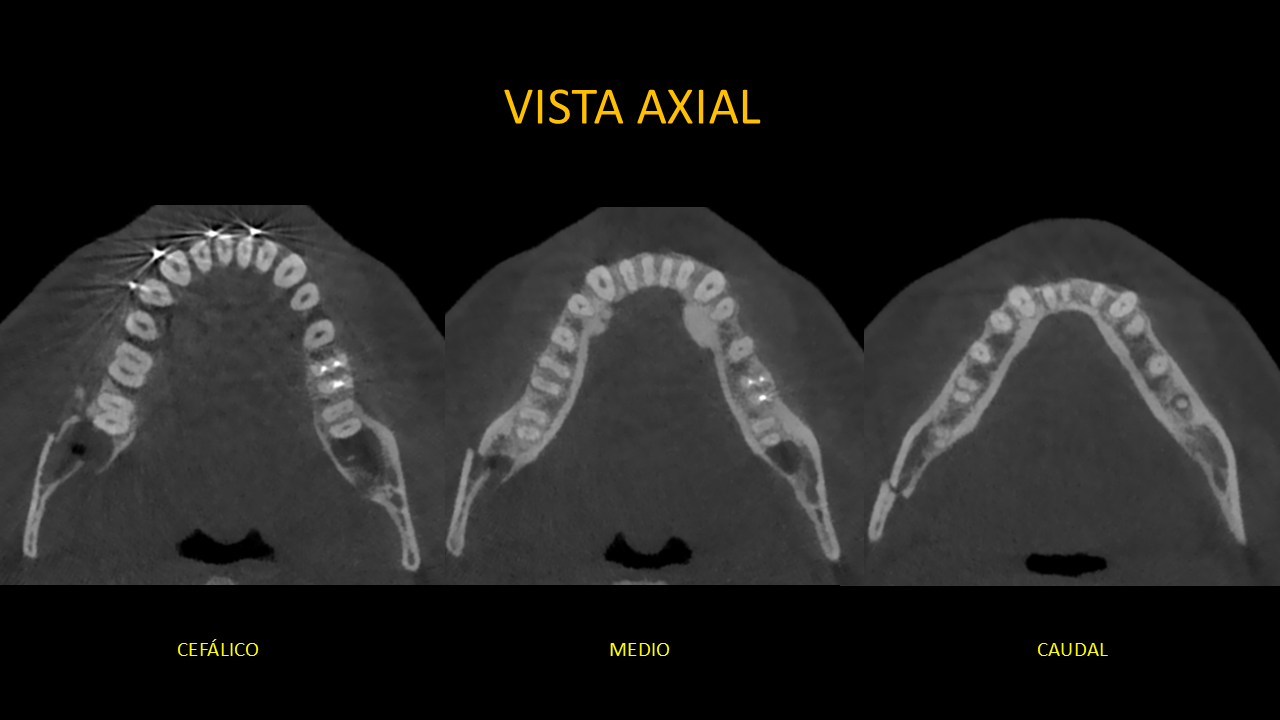

Figura 3: Vista Axial

En la vista axial (Figura 3) se observa que los fragmentos óseos están desalineados ya que el segmento posterior presenta un desplazamiento lateral con presencia de escalón en la tabla ósea vestibular y lingual.